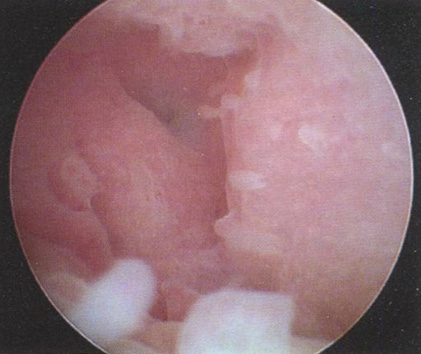

Заключение: полиповидная гиперплазия эндометрия

Рис. 3.5. Описание гистероскопической картины:

• полость матки треугольной формы, не деформирована;

• эндометрий бледно-розового цвета, в виде полиповидных разрастаний различной величины по всей полости матки;

• устья маточных труб не визуализируются.

Заключение: полиповидная гиперплазия эндометрия.

Гистологическое исследование: простая железистая ГПЭ.